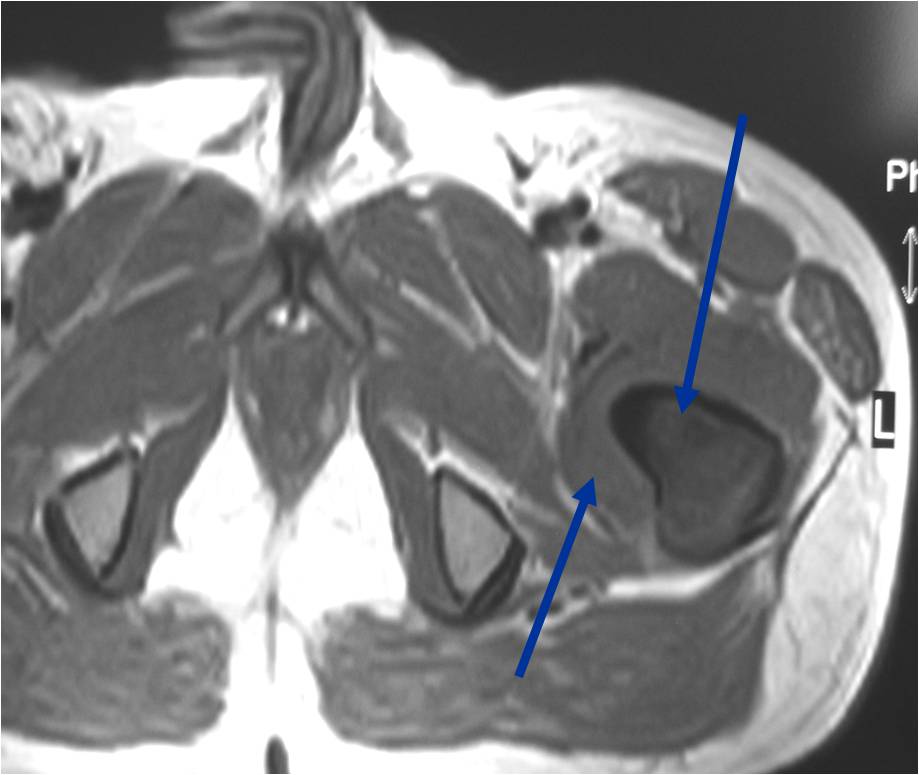

- Soft tissue mass— by CT (80%); by MRI (100%)

T2 Weighted MRI

TI Weighted MRI